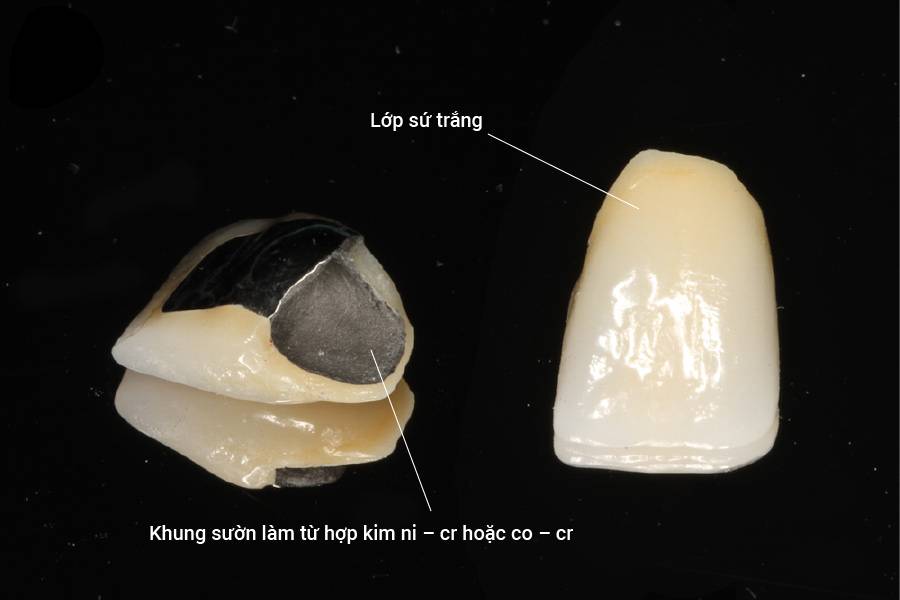

Hiện nay, bọc răng sứ luôn lựa chọn phổ biến trong các phương pháp phục hồi nha khoa. Tuy nhiên, không phải lúc nào răng sứ cũng

Bọc răng sứ là phương pháp hiệu quả giúp khắc phục những khuyết điểm của răng. Thông qua đó đem lại nụ cười trắng sáng và đều